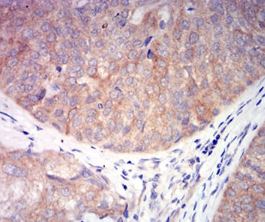

CHRNA6 Mouse Monoclonal antibody[5B6G8]

Species Reactivity:    Human

IHC    1/200 - 1/1000